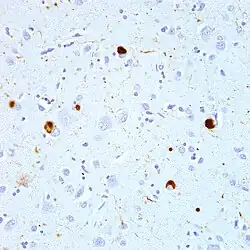

| Microscopic image of a Lewy body (arrowhead) in a neuron of the substantia nigra; scale bar=20 microns (0.02mm) | |